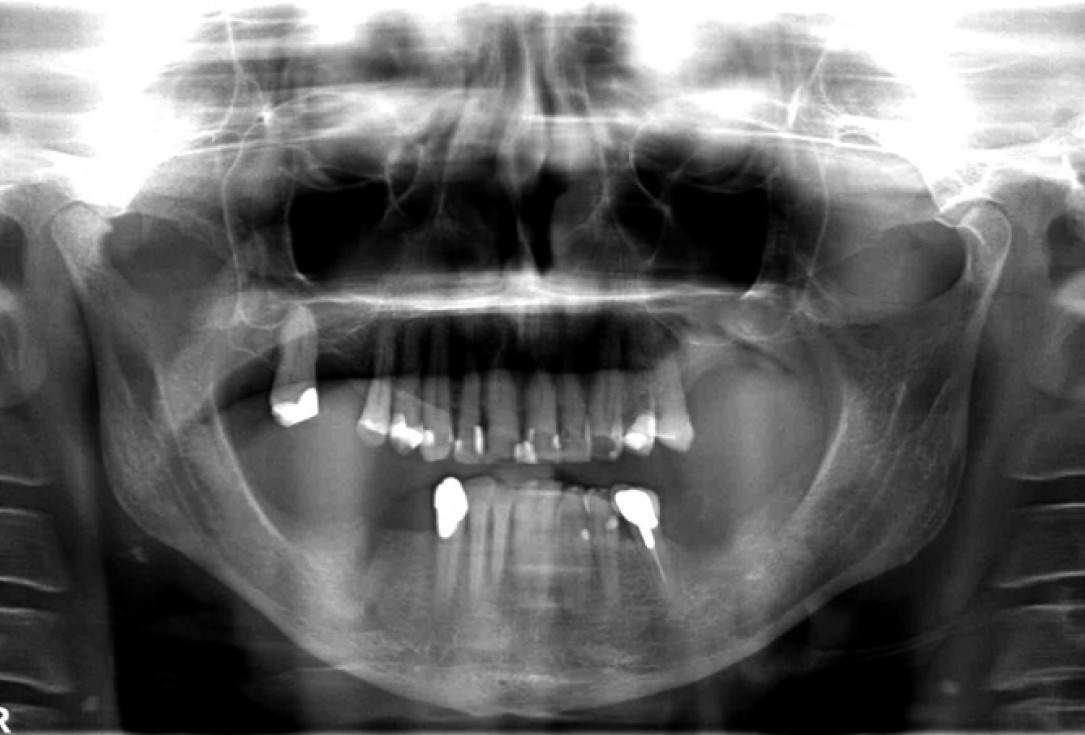

03/14 - Initial CBCT scan showing severe ridge atrophy in the right mandible

07/14 - Radiological situation post augmentation